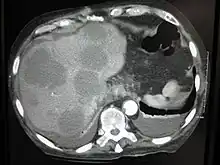

Cut surface of a liver showing multiple paler metastatic nodules originating from pancreatic cancer

Initially, nearby lymph nodes are struck early.[10] The lungs, liver, brain, and bones are the most common metastasis locations from solid tumors.[10]

Metastatic tumors are very common in the late stages of cancer. The spread of metastasis may occur via the blood or the lymphatics or through both routes. The most common sites of metastases are the lungs, liver, brain, and the bones[10]